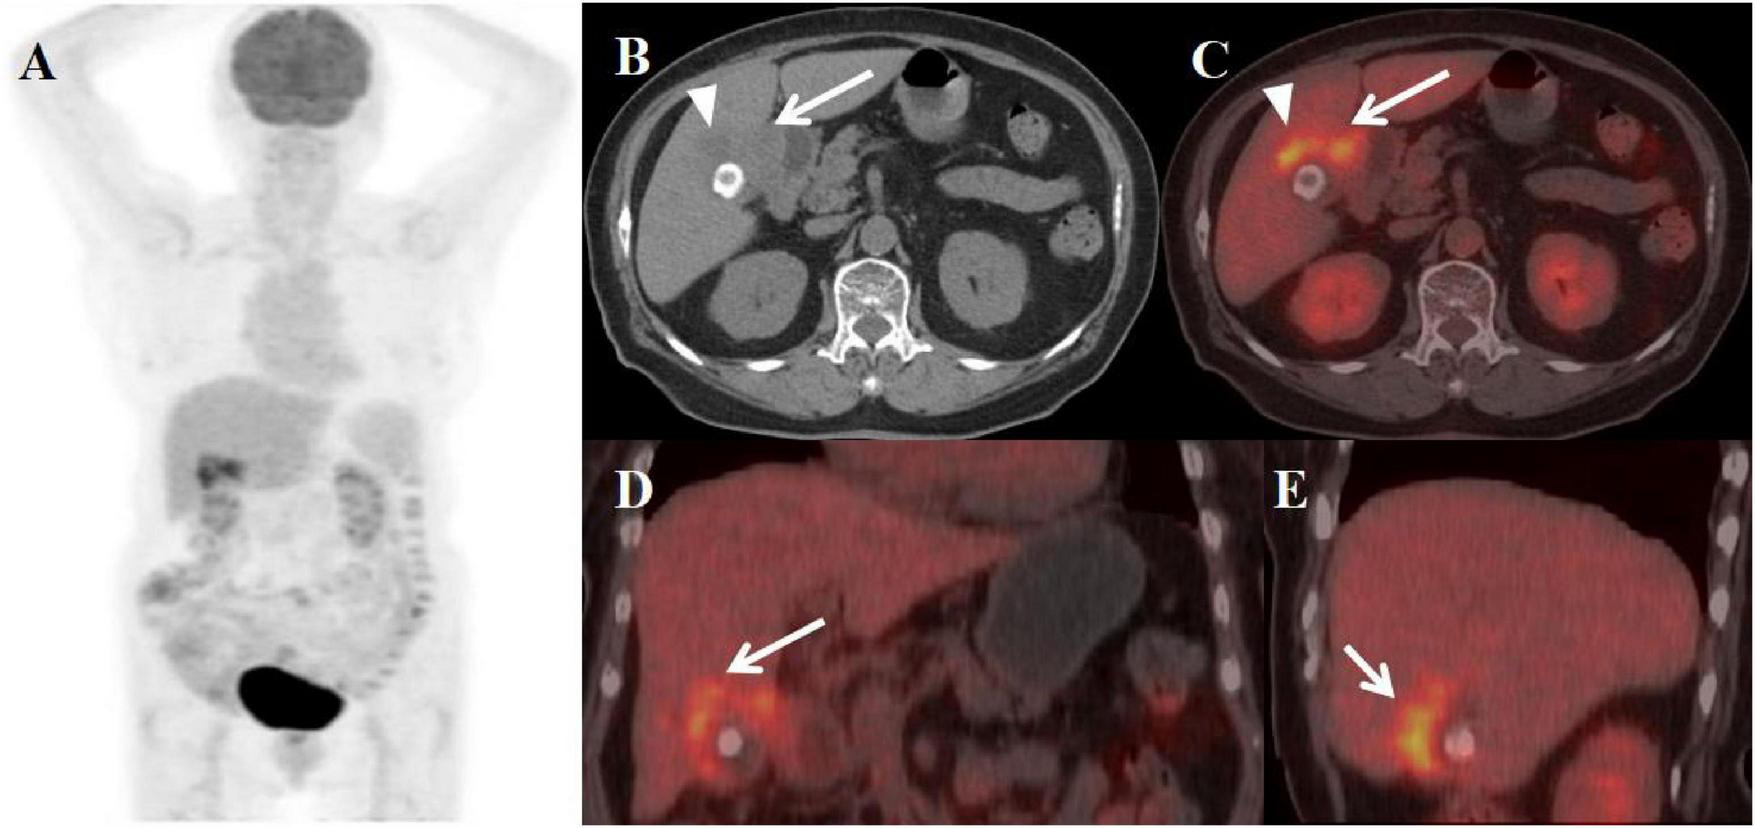

A 59-year-old female presented with abdominal pain for two weeks. Physical examination revealed a positive Murphy’s sign. The patient had a history of breast cancer surgery. Initial laboratory findings demonstrated moderate leukocytosis (WBC 12.50 × 109/L) with neutrophilic predominance (81%). Additionally, elevated inflammatory markers were observed, including C-reactive protein (CRP: 13 mg/L) and a mild increase in carbohydrate antigen 19-9 (CA19-9: 70.51 U/mL). All other tumor markers were within normal limits. Abdominal ultrasonography and MRI performed at an outside hospital demonstrated gallbladder wall thickening with multiple intraluminal gallstones. Given the clinical presentation, gallbladder malignancy could not be excluded, prompting referral to our institution for PET/CT evaluation. The PET/CT scan demonstrated an enlarged, adherent gallbladder with diffusely irregular wall thickening (maximum 12 mm) containing intramural hypodense nodules. The lesion showed intense FDG avidity (SUVmax 19.8) while maintaining mucosal integrity, though with loss of the normal hepatobiliary interface. Additional findings included inflammatory changes in pericholecystic fat and enlarged retroperitoneal lymph nodes (Figure 2). These features were initially interpreted as consistent with advanced gallbladder carcinoma with hepatic invasion and nodal metastasis. The patient subsequently underwent definitive surgical management including open cholecystectomy with partial hepatectomy. Final histopathological examination established the diagnosis of XGC, characterized by the hallmark findings of foamy histiocyte aggregates, chronic inflammatory infiltrates, and cholesterol clefts without evidence of malignancy.

Figure 2. Female, 59 years old. (A) (whole body MIP), (B, C) (Axial CT and fused axial PET-CT), (D, E) (Coronal CT and fused coronal PET-CT), and (F, G) (Sagittal CT and fused sagittal PET-CT). 18F-FDG PET/CT Imaging Findings: The gallbladder appears enlarged and adherent, demonstrating diffuse irregular wall thickening (maximum 12 mm) with intramural hypodense nodules (B, D, F, arrow ↑). Significant FDG uptake (SUVmax 19.8) was observed in the lesion, which preserved mucosal continuity despite disruption of the typical hepatobiliary interface (C, E, G, arrow ↑). Accompanying features comprised inflammatory infiltration of pericholecystic adipose tissue and enlargement of retroperitoneal lymph nodes.